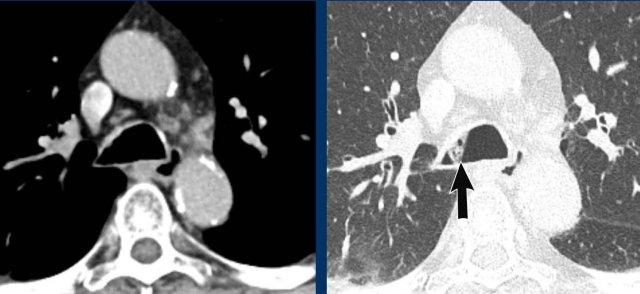

Cung động mạch chủ đôi

Bệnh nhân này có cung động mạch chủ đôi gây chèn ép khí quản.